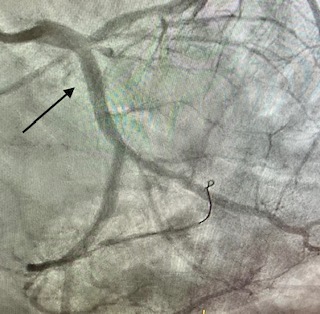

Angioplastia con stent en un infarto (arteria cerrada 100%)